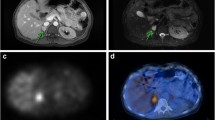

Diagnostic accuracy

There are scarce data on the use of [68Ga]DOTA-SSA for primary PHEOs/PPGL, although it has shown excellent results in localisation of these tumours when they are metastatic or extra-adrenal [90,91,92,93,94,95]. Moreover, [68Ga]DOTA-SSA PET has been found to be more sensitive than [123/131I]MIBG scintigraphy [96]. In a recent systematic review and meta-analysis, the pooled detection rate for [68Ga]DOTA-SSA PET/CT was 93% [95% confidence interval (CI), 91–95%], which was significantly higher (P < 0.001 for all) than that for [18F]-labelled fluorodihydroxyphenylalanine (FDOPA) PET/CT (80%; 95% CI, 69–88%), [18F]FDG PET/CT (74%; 95% CI, 46–91%), and [123/131I]MIBG scintigraphy (38%; 95% CI, 20–59%) [97]. Although interesting, this meta-analysis was compromised by the inclusion of PPGLs with various origins and a small number of PHEOs, as well as by limiting comparisons to lesion-based analyses.

Comparisons between [68Ga]DOTA-SSA PET/CT and [18F]FDOPA PET/CT have been performed in seven studies (five prospective, two retrospective) [63, 89, 98,99,100,101,102]. Separate data for PHEO could be extracted from one study [89], where [18F]FDOPA PET/CT showed better patient-based and lesion-based detection rates than did [68Ga]DOTA-SSA PET/CT in 10 cases (100% vs. 90% and 94% vs. 81%, respectively). In the published studies involving patients with extra-adrenal PGLs, [68Ga]DOTA-SSA PET/CT showed better patient-based and lesion-based detection rates than did [18F]FDOPA PET/CT (98% vs. 95% and 99% vs. 68%, respectively). According to a meta-analysis, [68Ga]DOTA-SSA PET/CT detected more SDHx-associated PPGL lesions than did [18F]FDG PET/CT [103]. In a recent non-comparative study from the Royal North Shore Hospital in Australia, [68Ga]DOTATATE PET/CT exhibited sensitivity of 84% (21/24) for the detection of PHEO and 100% (7/7) for the detection of PGL [104]. A higher clinical value for [68Ga]DOTA-SSA PET/CT than for [18F]FDG PET/CT was also observed in a paediatric population [102]. Among the various susceptibility genes, EPAS1 (HIF2A) and, possibly, PHD1/2 and FH remain exceptions because they cause PPGLs that concentrate a lesser amount of [68Ga]SSAs relative to the amount concentrated by SDHx-associated PPGLs [105]. The underlying mechanism for this phenotype is currently unclear. Overall, it seems that [68Ga]DOTA-SSA PET/CT is the most sensitive tool for the detection of HNPGLs (particularly those associated with SDHD), which may be very small and/or fail to concentrate [18F]FDOPA in a sufficient amount. On the other hand, [18F]FDOPA PET/CT may be more effective than [68Ga]DOTA-SSA PET/CT in the detection of PHEOs.